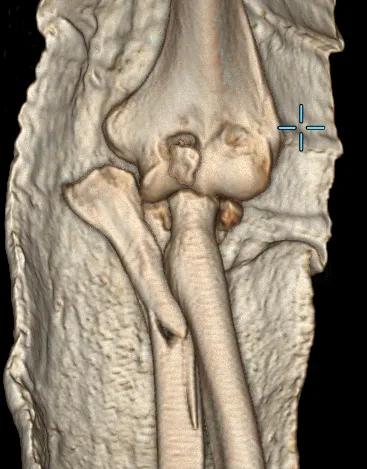

左肘關節CT平掃+三維檢查提示

左肘關節面對位欠佳

左尺骨鷹嘴及橈骨頭骨折

周圍軟組織腫脹